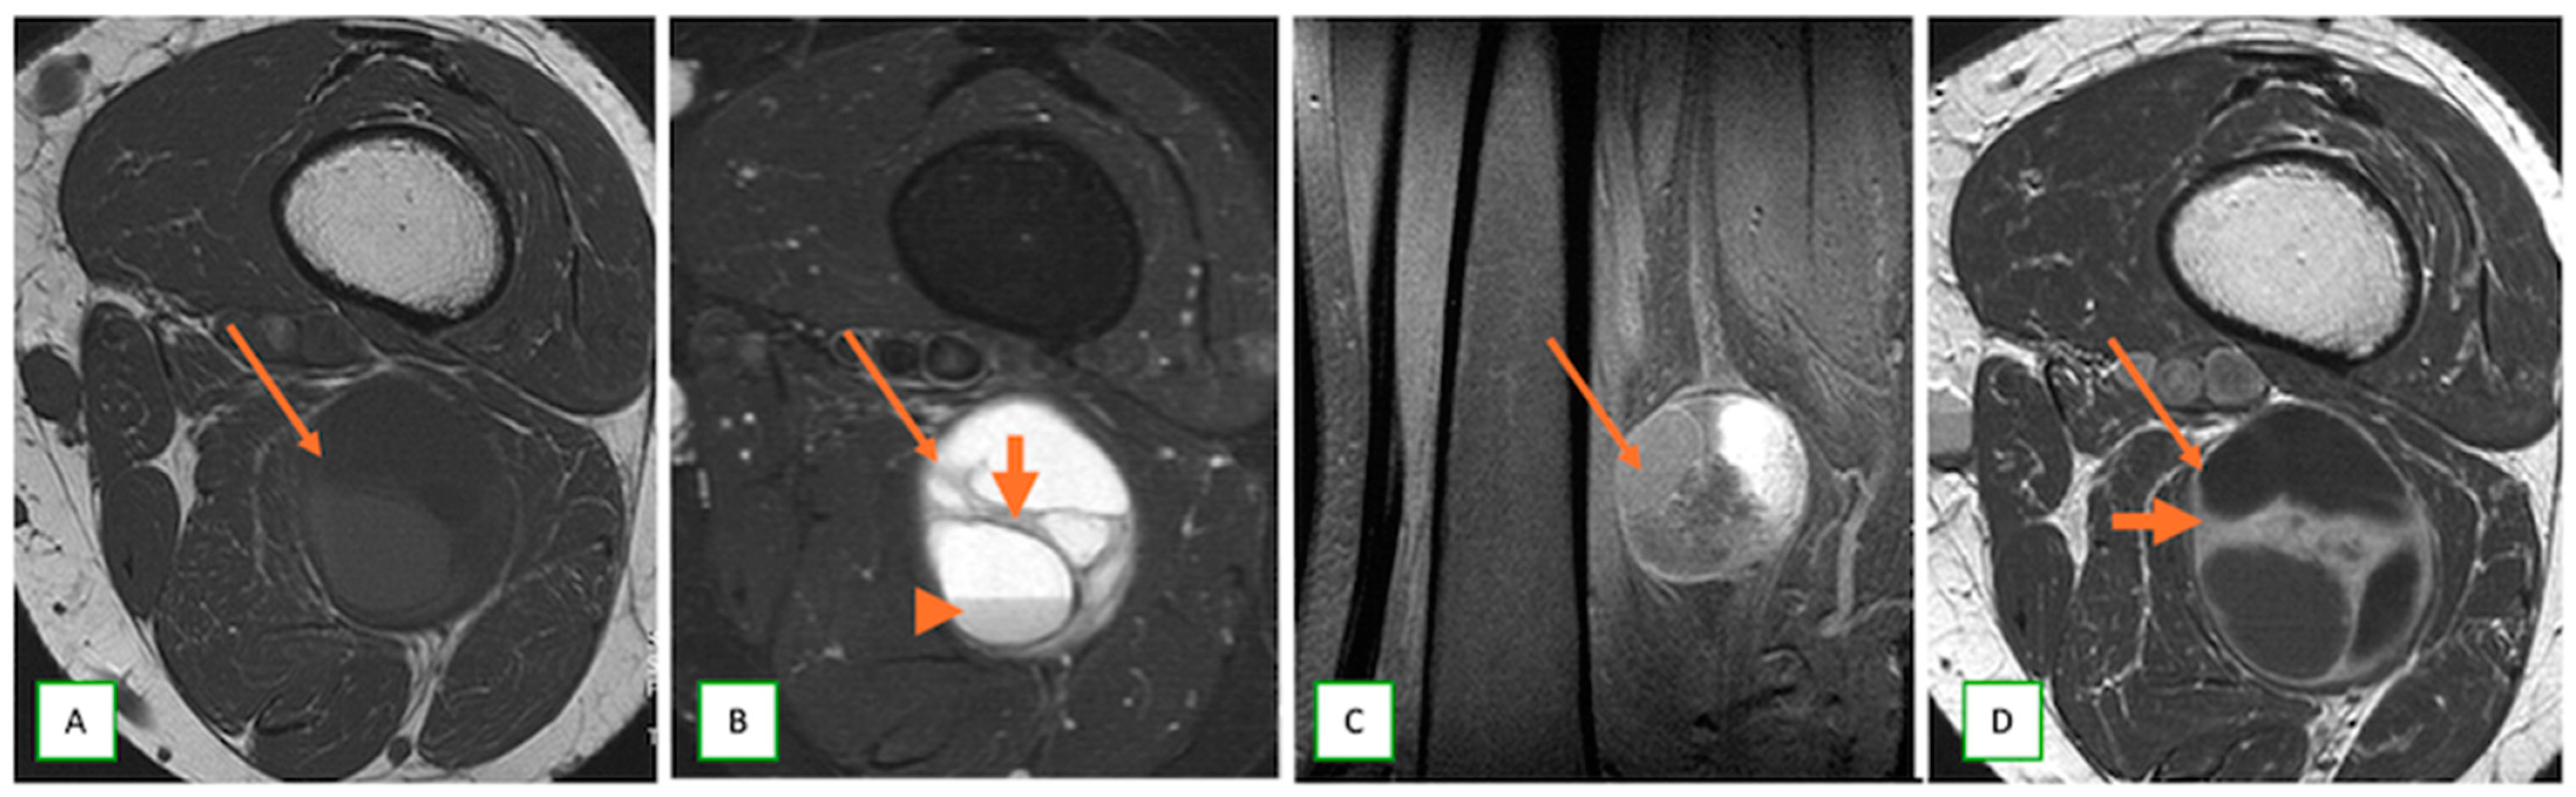

- Primary Sarcomas: Soft-tissue sarcomas are uncommon, accounting for just over 1% of adult malignancies. Synovial sarcoma, clear cell sarcoma, and epithelioid sarcomas are known to involve peripheral nerves. CT/MR reveals a large soft tissue mass with areas of necrosis or calcification and heterogeneous contrast enhancement. F-18 FDG uptake is useful for both tumor staging and treatment assessment (Figure 26, Figure 27 and Figure 28).